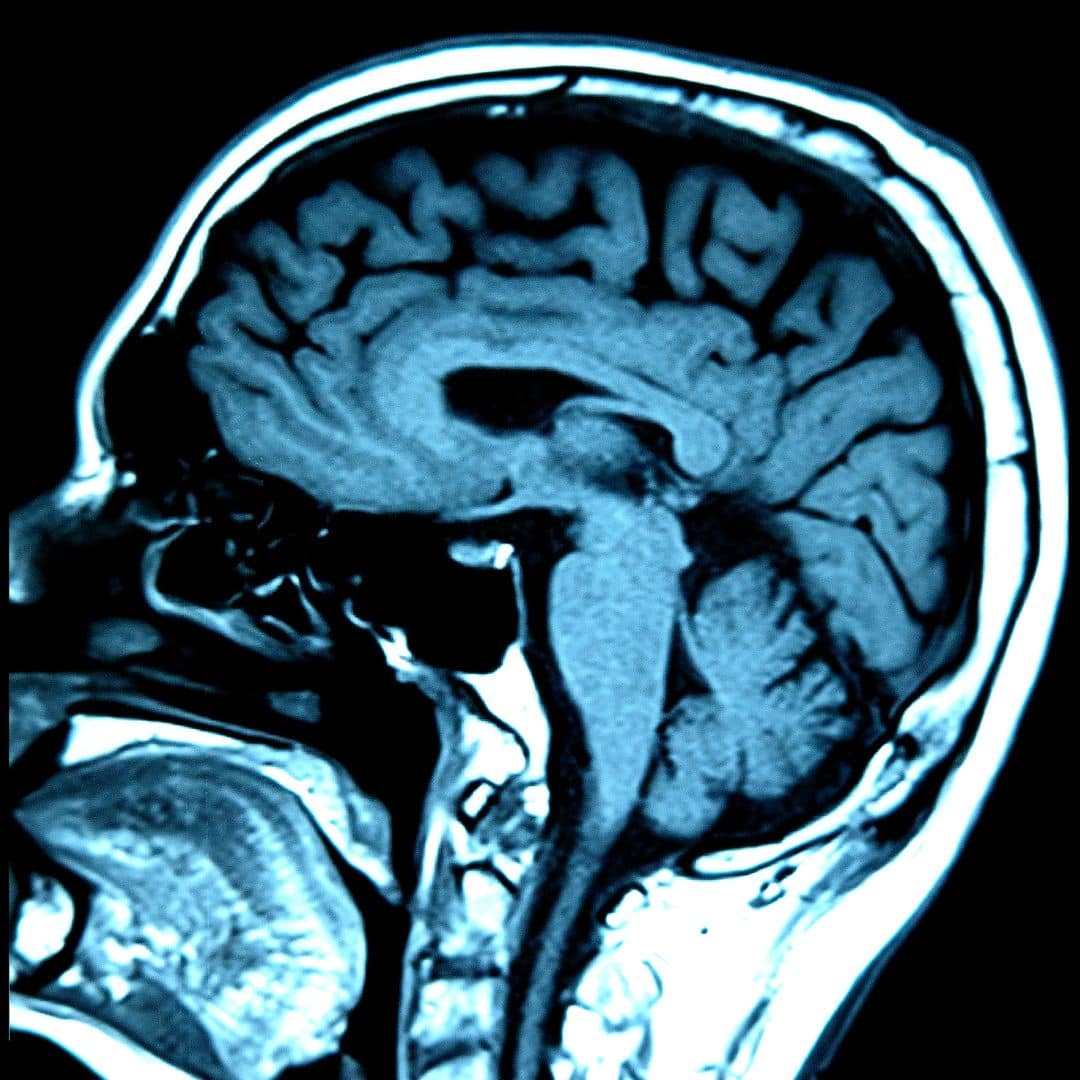

El Síndrome de Sensibilidad Central altera la forma en que el cerebro procesa dolor, energía y estímulos. No es psicológico: es una desregulación medible en el QEEG, donde aparece una baja amplitud en todos los rangos de ondas cerebrales. En este artículo explico qué es, cómo reconocerlo y por qué la tDCS puede mejorar sus síntomas al restaurar la actividad eléctrica del cerebro.

Hoy sabemos que el SSC tiene una base neurofisiológica clara, que puede medirse con QEEG (electroencefalografía cuantitativa) y que puede tratarse mediante técnicas de neuromodulación no invasiva como la tDCS.

Aquí es donde la evidencia neurofisiológica se vuelve muy clara. En los registros de QEEG, el patrón más característico del SSC es la baja amplitud generalizada en todas las ondas cerebrales. Esto significa que las neuronas están funcionando por debajo de su nivel óptimo, con menor intensidad y eficiencia.

No es subjetivo. No es psicológico. Es medible. Cuando la amplitud está reducida, las redes cerebrales pierden capacidad para sostener un funcionamiento estable.